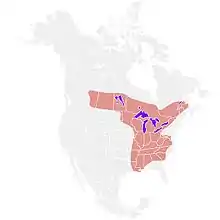

Blastomycosis is endemic to the eastern United States and Canada, especially the Ohio and Mississippi River valleys, the Great Lakes, and the St. Lawrence River valley.[6] In these areas, there are about 1 to 2 cases per 100,000 per year.[13] Less frequently, blastomycosis also occurs in Africa, the Middle East, India, and western North America.[8][14] Blastomycosis also affects a broad range of non-human mammals, and dogs in particular are an order of magnitude more likely to contract the disease than humans.[15] The ecological niche of Blastomyces in the wild is poorly understood, and it is unknown if there are any significant host animals.[16]